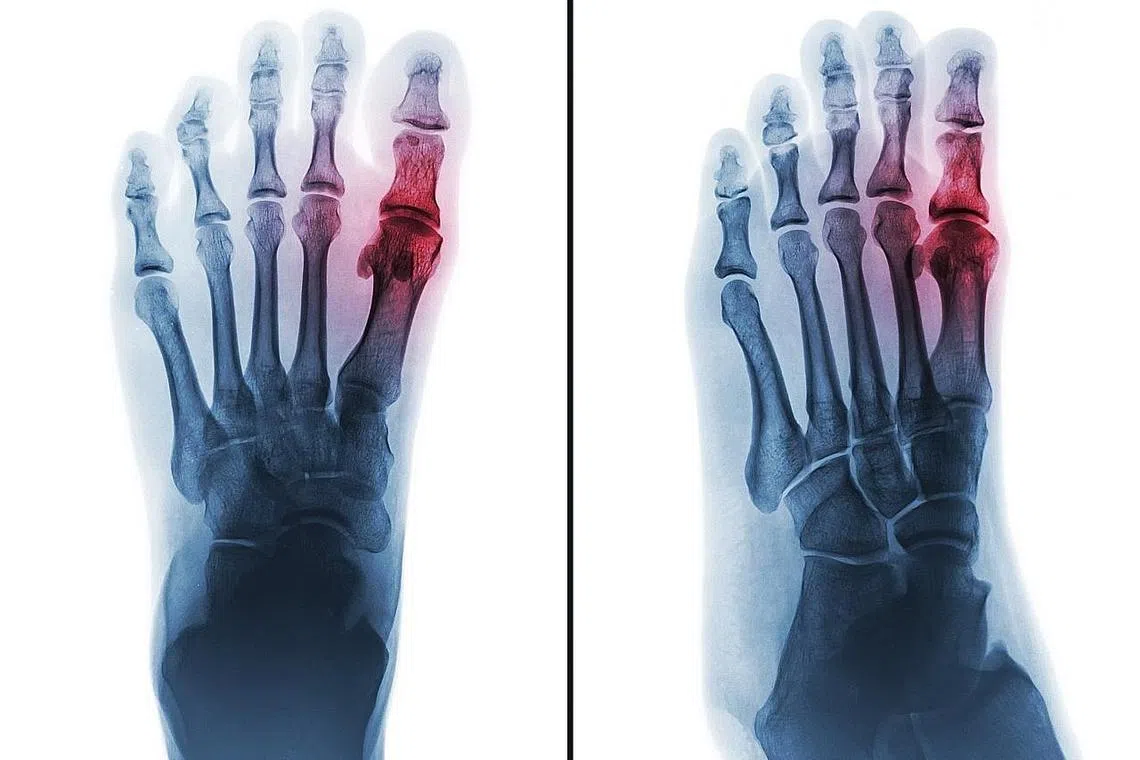

ANTARA PENYAKIT PALING LAMA: Gout adalah sejenis penyakit disebabkan berlebihan asid urik di dalam badan. Bagi penghidap gout, asid urik yang berlebihan tidak dibuang dan berkumpul di dalam sendi. - Foto ISTOCKPHOTO -